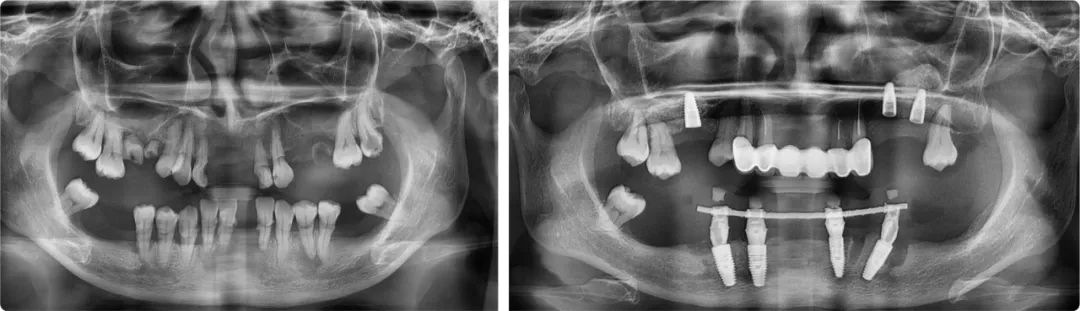

在謝海洋完成的種植案例中,不乏一些高難度治療。一位48歲的藏族女性全口缺牙較多,想做即拔即種。原計劃下側(cè)前牙做種植固定橋修復(fù),后牙保留,但顧客再次來院時后牙已搖搖欲墜,沒有保留價值,治療方案必須調(diào)整。

“由于患者后牙牙槽骨垂直性吸收,拔牙后需要種植的位置距離神經(jīng)管太近,無法種植。為解決這個問題,前牙區(qū)的四顆我采用了傾斜種植,盡量把修復(fù)的牙位往后移,彌補她后牙區(qū)的咀嚼功能。”

手術(shù)中,謝海洋通過數(shù)字化導(dǎo)板精準(zhǔn)定位,避開頦孔和下牙頜神經(jīng)管,完成了下半口即拔即種治療。“有兩個種植點位一側(cè)是神經(jīng)管,一側(cè)是之前種植的植體,位置不容有一絲偏差,否則要么種植失敗,要么造成不可逆轉(zhuǎn)的下唇麻木。”術(shù)后CBCT顯示,種植體距離神經(jīng)和頦孔0.3-0.5毫米,屬于安全距離內(nèi)。

患者術(shù)前術(shù)后全景片

“如果沒有數(shù)字化導(dǎo)板技術(shù),這例手術(shù)不可能完成,但更多的案例還是要靠醫(yī)生的手上功夫、臨床經(jīng)驗和責(zé)任心。”謝海洋遇到過不少口腔條件不好的患者,有一些患者還不接受缺牙期,希望種植當(dāng)天就能用上牙。